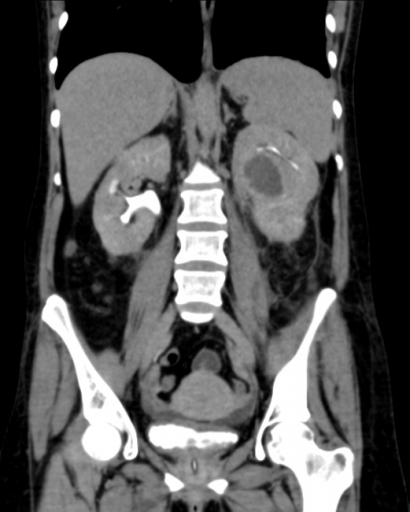

Нефрокальциноз (кальцинаты в почках) - это отложения солей кальция в почечных тканях с образованием конкрементов различного размера . Конкременты представляют собой твердые включения из солей в области инфильтрационного воспаления . Нефрокальциноз может возникать как сопутствующее заболевание при дисфункции почек и мочевыводящей системы .

Кальцинаты в почках - это кристаллы из солей кальция, которые откладываются в почечной ткани и приводят к рубцеванию органов . В 8 из 10 случаев в паренхиме и мозговом веществе почки . . .